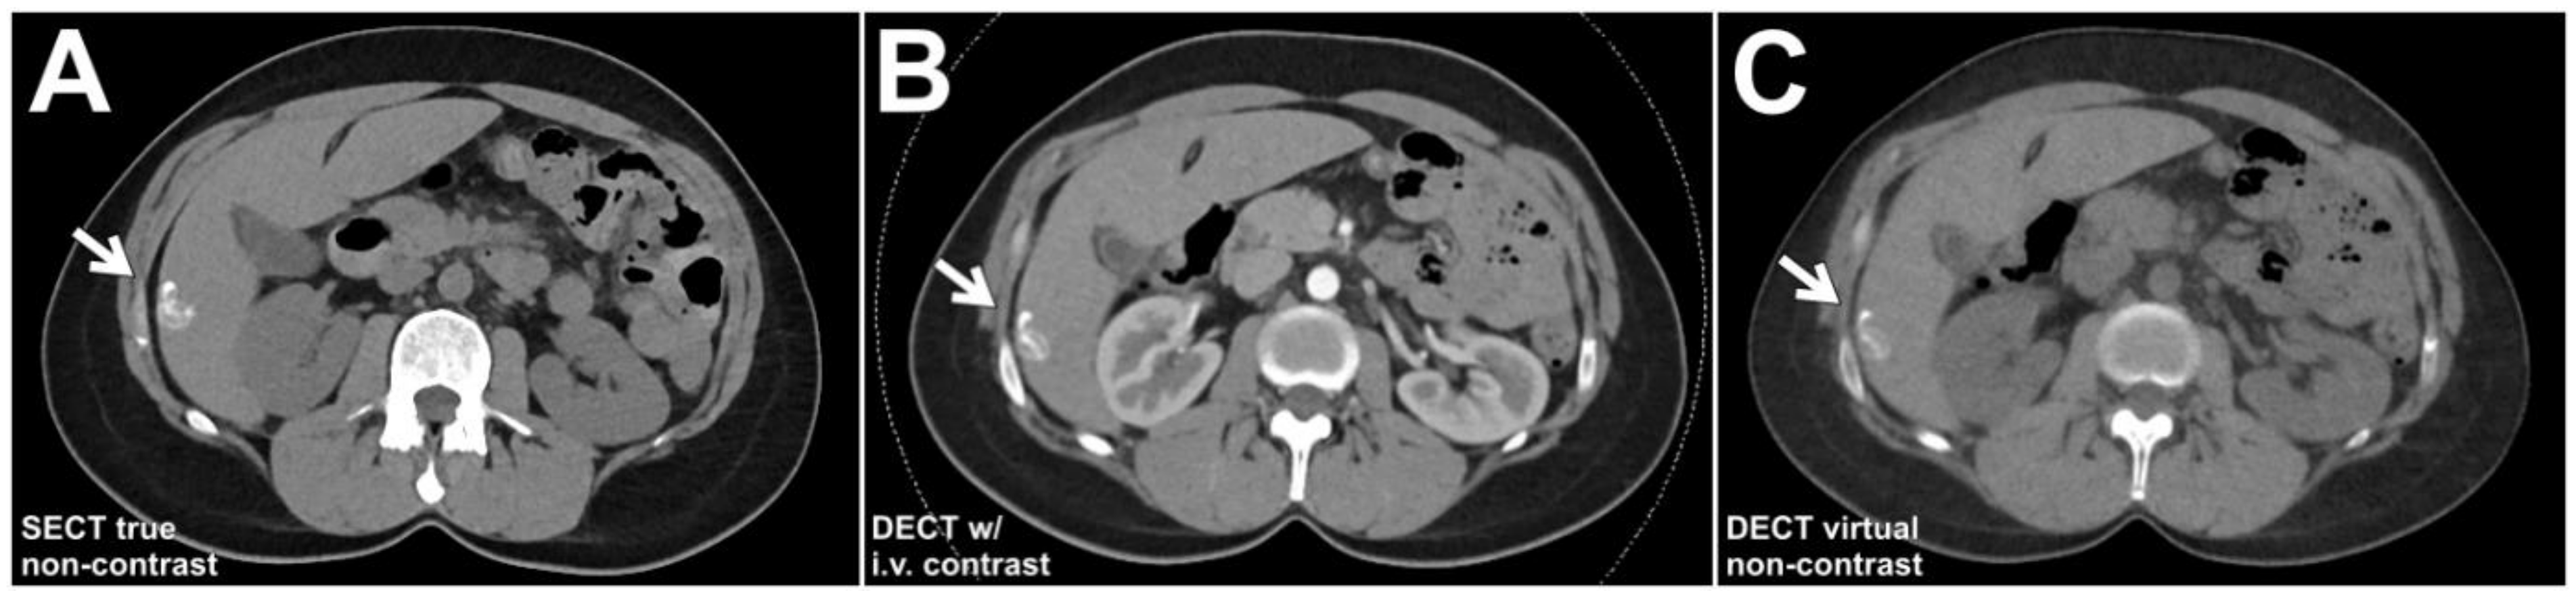

- Graser, A.; Johnson, T.R.C.; Hecht, E.M.; Becker, C.R.; Leidecker, C.; Staehler, M.; Stief, C.G.; Hildebrandt, H.; Godoy, M.C.B.; Finn, M.E.; et al. Dual-Energy CT in Patients Suspected of Having Renal Masses: Can Virtual Nonenhanced Images Replace True Nonenhanced Images? Radiology 2009, 252, 433–440. [Google Scholar] [CrossRef]